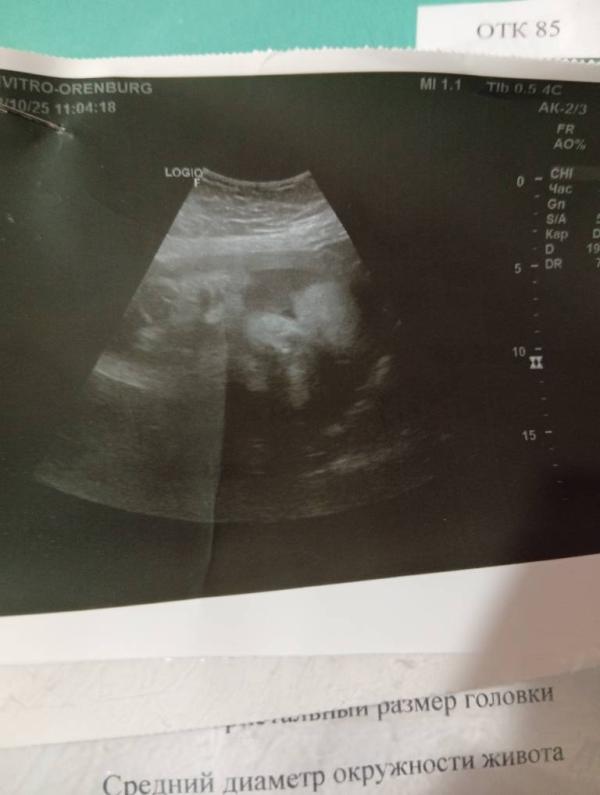

Приветик всем съездила я на узи ещё раз переживала что шевеления сильные очень. Но с малышкой все хорошо выглядит на 35-36 недель, хотя у меня сейчас 33 недели. Вес поднабрала дочь 2830, и самое главное перевернулась . и дату пдр теперь по узи на 4.11.25 начало месяца. Даже показала своё личико😍😍